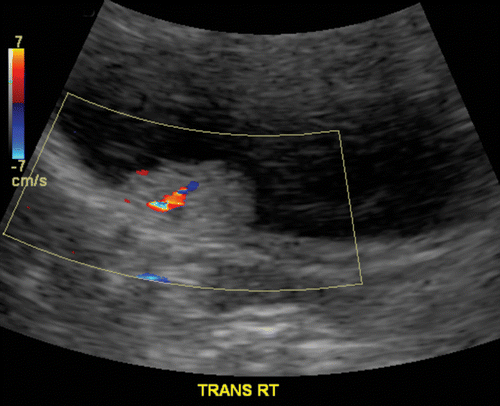

Newborn with a hypoechoic lesion on ultrasound

A

MESOBLASTIC NEPHROMA.

Wilms like tumor, but <1 month old.

Solid renal tumor of infancy. Fetal hamartoma. Most common renal tumor in the first month of life.Involves renal sinus.